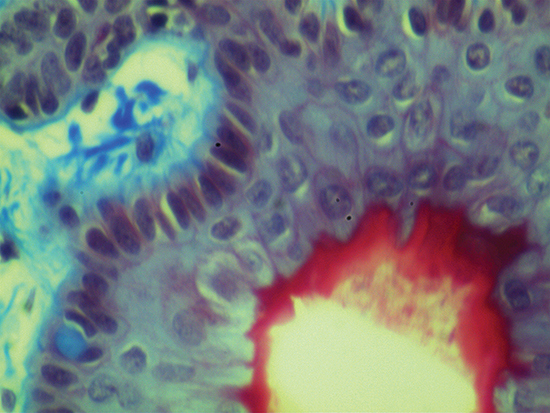

Figure 4 demonstrates 50X magnification - the highest magnification easily achieved without mechanical stages or piezo actuators stabilizing the infinity corrected objective and image plane. At this magnification, slight vibrations from an illuminator or computer’s fan can cause the video feed to dramatically shake and jump out of focus. Figure 4 was captured using #59-879 50X M Plan Apo Objective. It has a numerical aperture of 0.55, field of view on a ½" sensor of 0.128mm x 0.096mm, and a resolving power of 0.5μm. The depth of focus for this particular objective is only 0.9μm, making focusing a tedious process if the appropriate mechanics are not utilized. In Figure 4, the cellular membrane and intracellular components are very clear and vibrant compared to the previous 5X, 10X, and 20X images. Also, the size and shape of the cellular constituents become truly evident. When comparing Figure 1 (5X magnification) to Figure 4 (50X magnification), the increase in magnification is immediately apparent. The resolving power increases by four and the field of view is minimized by a factor of twenty. When imaging at 50X magnification, high light intensity and contrast is required to increase illumination and to digitally adjust shutter speed and gain. The digital settings can be set to automatically compensate for darkness or frame rate – excellent for constructing a digital video microscope for the first time. For additional details on constructing one with off-the-shelf components, please read Digital Video Microscope Objective Setups.

Figure 4: Trichrome Stain of Dermal Tissue Samples at 50X Magnification Using #59-879 Objective